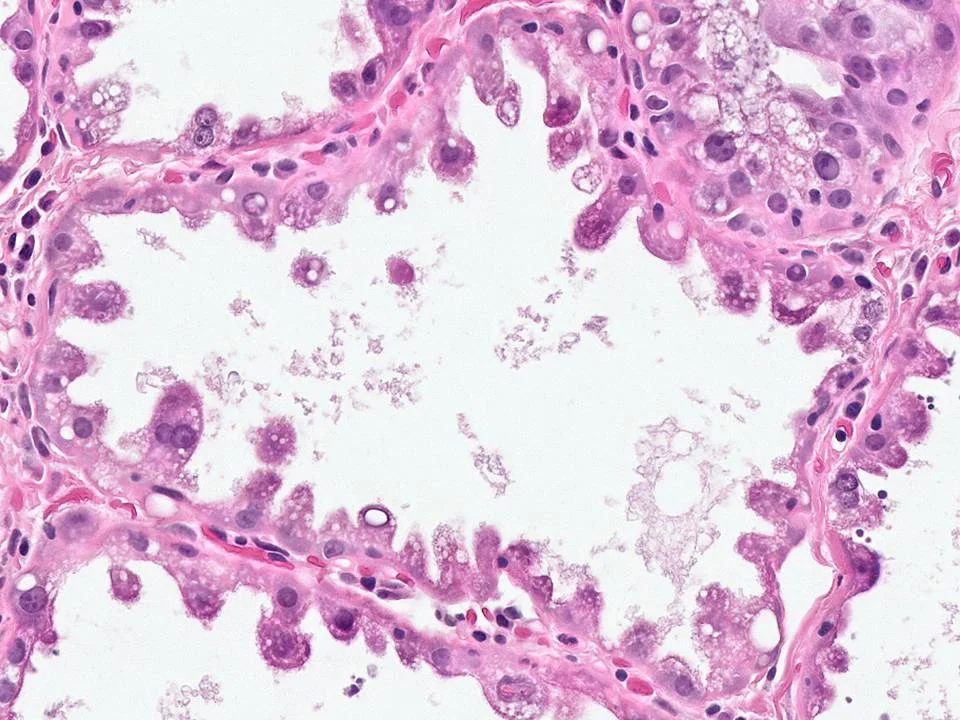

Mucinous Carcinoma

Mucinous carcinoma is characterized by abundant production of extracellular mucin with admixed clusters of tumor cells. The extent of extracellular mucin production varies from tumor to tumor. Histologically, small clusters of tumor cells are seen dispersed within pools of extracellular mucin. Thin fibrous septae with thin-walled blood vessels are identified.

Mucinous carcinomas can be classified based on cellularity into Type A (paucicellular) and Type B (highly cellular). Type B mucinous carcinomas often have endocrine differentiation.

Mucinous carcinomas are usually ER positive and about 70% are PR positive. They usually do not show HER2 overexpression.